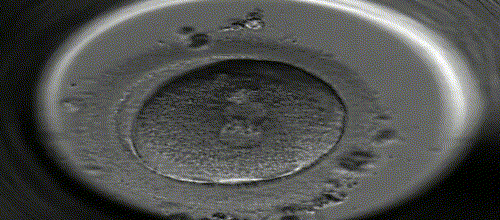

当一个获能的精子进入一个次级卵母细胞的透明带时,受精过程即开始。直至卵原核和精原核的染色体融合在一起时,则标志着受精过程的完成。

受精卵开始进行有丝分裂的同时,在输卵管内借着输卵管蠕动和纤毛推动,向子宫腔方向移动,约在受精后第3~4日,分裂成由16个细胞组成的实心细胞团,称桑椹胚,继续发育成为囊胚。